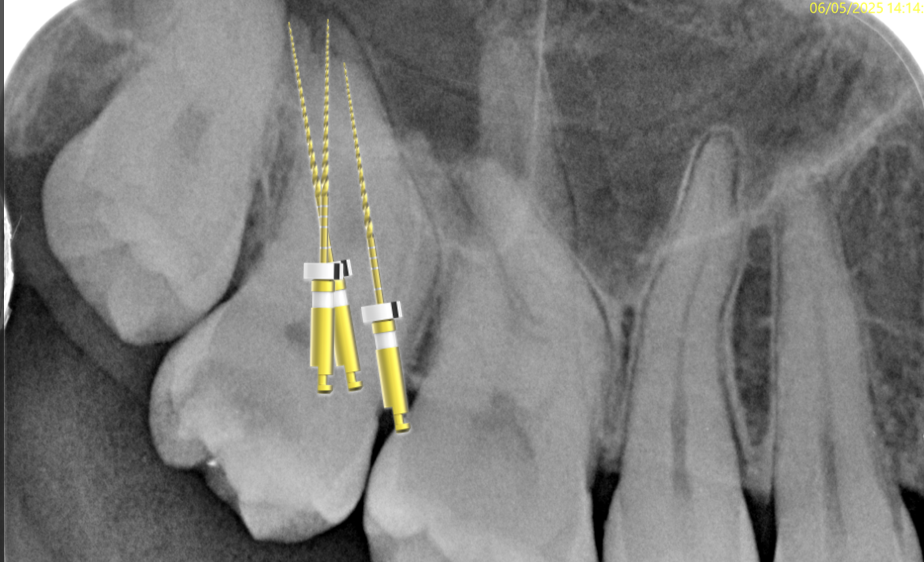

Fig. 8

After pre flaring, I was able to reach the working length in all the root canals with the R1 file.